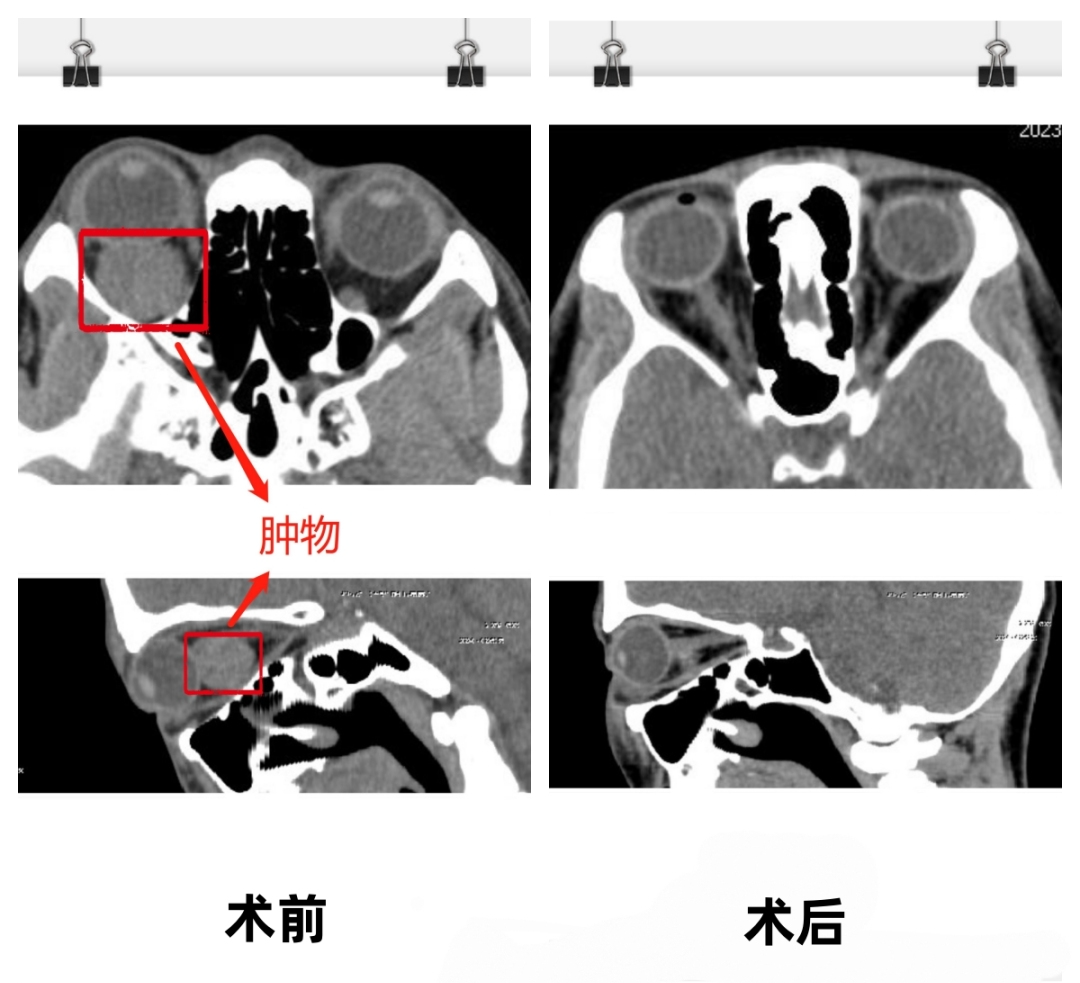

经过检查发现她的右眼视力只有 0.2,验光+4.00 度远视。随后眼眶 CT 平扫提示右侧眼眶肿物,吕医师考虑可能是巨大海绵状血管瘤,建议黎女士进一步检查眼底、视野以及眼眶增强 MRI。

经过一系列检查后发现,黎女士的肿瘤生长在眼球后部眶内,随着肿瘤逐渐增大压迫视神经,随时有失明的危险。吕碧副主任详细告诉黎女士病情后,建议她尽快手术切除肿瘤。

该手术切除肿瘤约 2.0 cm×1.8 cm 大小,病理检查提示右眼眼眶海绵状血管瘤。

术中及术后未发生并发症,黎女士眼球突出症状也得到大大改善,视力更是从原来的 0.2 恢复到 1.2。